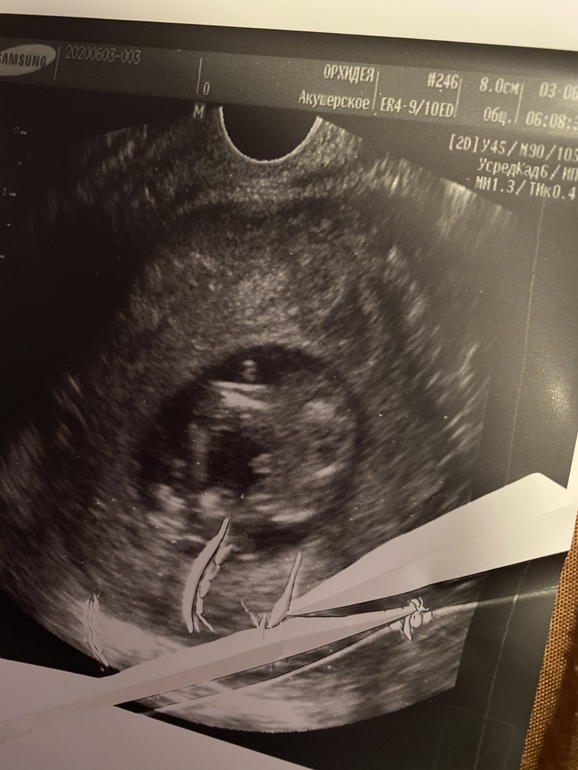

УЗИ, КТГ, доплеркакой пол вам кажется?) узист сделал предположение, но не уверен . Знаю что рано, но кому то на этом сроке точно говорят((

Это мальчик))Прям конкретный такой))

Вам с мальчиками говорили и показывали на таком сроке? Просто не понятно, узист по половому бугорку сначала говорит девочка похоже, а потом увидел что торчит и говорит мальчик

Мальчиков вообще видно сразу)У вашего между ног не перепутать уже)))